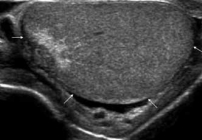

USG jąder w Lublinie w Centrum Medycznym PROVIVO to bezpieczne i nieinwazyjne badanie obrazowe, które pozwala ocenić zawartość worka mosznowego, w tym jądra, najądrza, ich osłonki oraz obecność żylaków powrózka nasiennego.

Badanie umożliwia ocenę jąder, najądrzy, osłonek jąder oraz struktur znajdujących się w obrębie worka mosznowego. Pozwala także wykryć obecność żylaków powrózka nasiennego, które mogą mieć znaczenie kliniczne i wpływać na dalsze postępowanie diagnostyczne lub lecznicze.

USG jąder jest jednym z podstawowych badań obrazowych wykorzystywanych w diagnostyce zmian w obrębie moszny. Dzięki niemu lekarz może lepiej ocenić przyczynę dolegliwości i zdecydować o dalszych krokach.